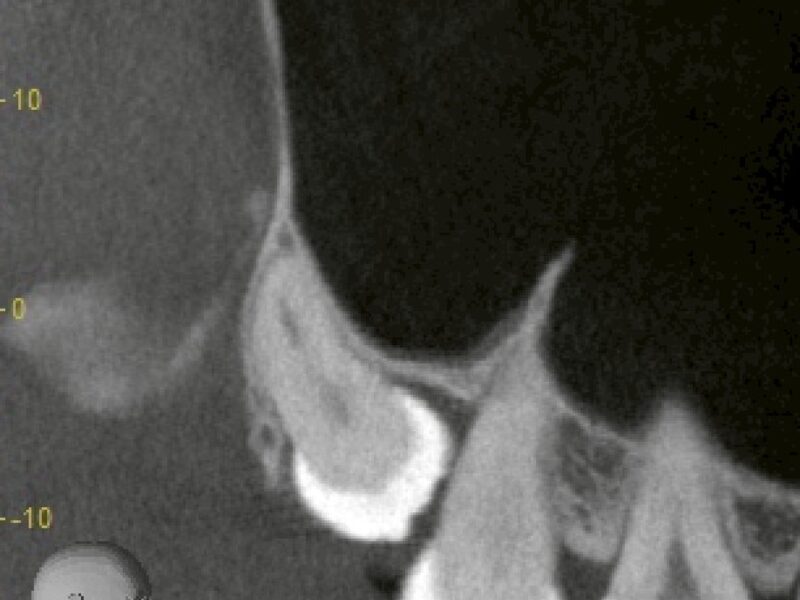

特徴4高精度診断を可能にする「歯科用CT」 -